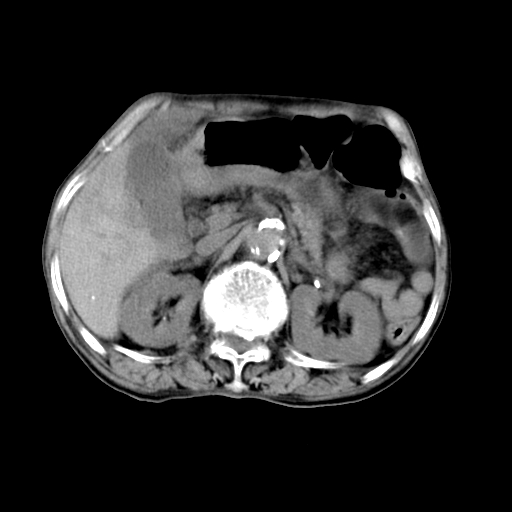

标题: CT19149:女,68岁,腹胀、恶心两周。 [打印本页]

标题: CT19149:女,68岁,腹胀、恶心两周。

女,68岁,腹胀、恶心两周,先做ct平扫,当时家属不同意强化,6天后家属要求增强扫描。

考虑肝癌。

1、胃窦癌; 2、局灶性脂肪肝。

1、胃窦癌?建议行胃镜!; 2、局灶性脂肪肝。

1.局灶性脂肪肝;2.胃窦癌可能,建议行进一步检查。

1)不排除胃窦癌;建议行胃镜检查。 2)局灶性脂肪肝。

1)不排除胃窦癌;建议行胃镜检查。 2)局灶性脂肪肝。腹水。

考虑:胃窦ca,腹水,脂肪肝

1)胃窦壁厚,考虑胃窦癌?建议行胃镜检查。 2)局灶性脂肪肝。

支持考虑1、胃窦癌?建议行胃镜!; 2、局灶性脂肪肝。  3、双侧胸腔积液,胸膜增厚

不均匀脂肪肝,胃腔改变须结合钡餐或胃镜观察

1)局灶性脂肪肝。2)胃窦癌可能,建议行胃镜检查。